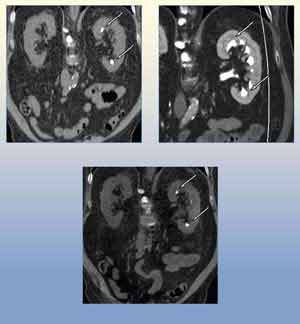

• Image of a dual energy CT urogram study

Iodine Removal

Dual energy CT can be used to electronically remove iodine signal from a contrast-enhanced dual energy scan. In this dual energy CT urogram study, the renal calculus (arrow) visible in the true non-contrast scan (Top left) is hidden in the contrast-enhanced scan (Top right). Through the use of the "virtual, non-contrast" dual energy application, the iodine can be electronically removed, revealing the renal calculus (Bottom). This application could potentially replace the need for the true non-contrast portion of a CT urogram, thus lowering patient dose.